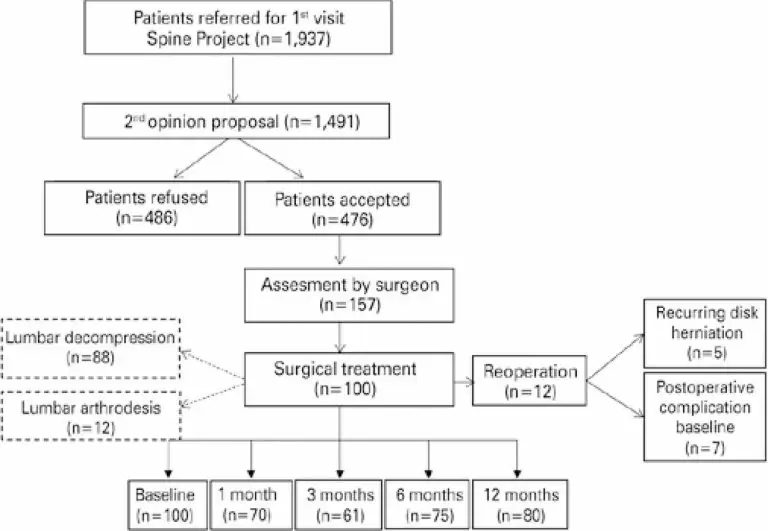

Clinical outcome analysis in surgical patients enrolled in a Second Opinion Program in spine surgery

DOI: 10.31744/einstein_journal/2022AO5791

ABSTRACT Objective To analyze pain, functional capacity, quality of life, anxiety and depression outcomes in patients undergoing lumbar spine surgery following use of the Second Opinion Program, and to present disagreements regarding diagnoses and therapeutic indications between the first and second opinions. Methods A prospective, observational cohort study with 100 patients enrolled in the Second Opinion Program who underwent lumbar spine surgery. Questionnaires addressing pain intensity, level of disability, quality of life, anxiety and depression were applied prior to and […]

Palavras-chave: Ansiedade; Artrodese; Depressão; Dor lombar; Manejo da dor; Qualidade de vida; Encaminhamento e consulta; Spinal diseases/surgery; Resultado de tratamento